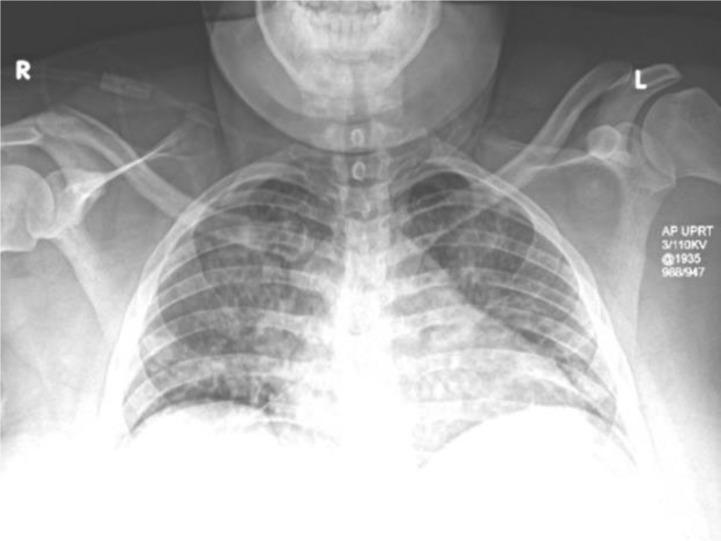

COVID-19 与 34 周妊娠伴严重特征的子痫前期。

COVID-19 and preeclampsia with severe features at 34-weeks gestation.

The evolving coronavirus disease 2019 (COVID-19) pandemic, caused by severe acute respiratory syndrome coronavirus 2 (SARS-CoV-2), has led to a rapid expansion of knowledge on the disease's clinical manifestations, laboratory and radiographic abnormalities, and patient trajectories. One area of particular focus is the effect that this illness may have on pregnancy and maternal-fetal disease. As of April 24, 2020, we identified 55 English language reports in the scientific literature summarizing data for 339 women and 258 fetuses and neonates. The majority of these data have focused on maternal-fetal transmission and neonatal outcomes. One systematic review and meta-analysis including the spectrum of coronaviruses [Severe Acute Respiratory Syndrome (SARS), Middle East Respiratory Syndrome (MERS), and COVID-19] in pregnancy noted increased rates of adverse outcomes associated with this group of infections. Here, we report the case of a COVID-19 positive woman presenting to our emergency department (ED) at 34 weeks gestation with preeclampsia. This case highlights the unique diagnostic and therapeutic challenges associated with treating patients with these concomitant diseases.

不断演变的 2019 年冠状病毒病(COVID-19)大流行是由严重急性呼吸系统综合征冠状病毒 2(SARS-CoV-2)引起的,这导致人们对该病的临床表现、实验室和影像学异常以及患者病程迅速扩展了认识。其中一个特别关注的领域是这种疾病可能对妊娠和母婴疾病的影响。截至 2020 年 4 月 24 日,我们在科学文献中发现了 55 篇英文报告,这些报告汇总了 339 名妇女和 258 名胎儿和新生儿的数据。这些数据主要集中在母婴传播和新生儿结局上。一项包括 SARS、MERS 和 COVID-19 在内的冠状病毒妊娠谱的系统评价和荟萃分析指出,与这组感染相关的不良结局发生率增加。在这里,我们报告了一例 COVID-19 阳性妇女在 34 周妊娠时因子痫前期到我们的急诊就诊的病例。该病例突出了与治疗这些合并疾病相关的独特诊断和治疗挑战。